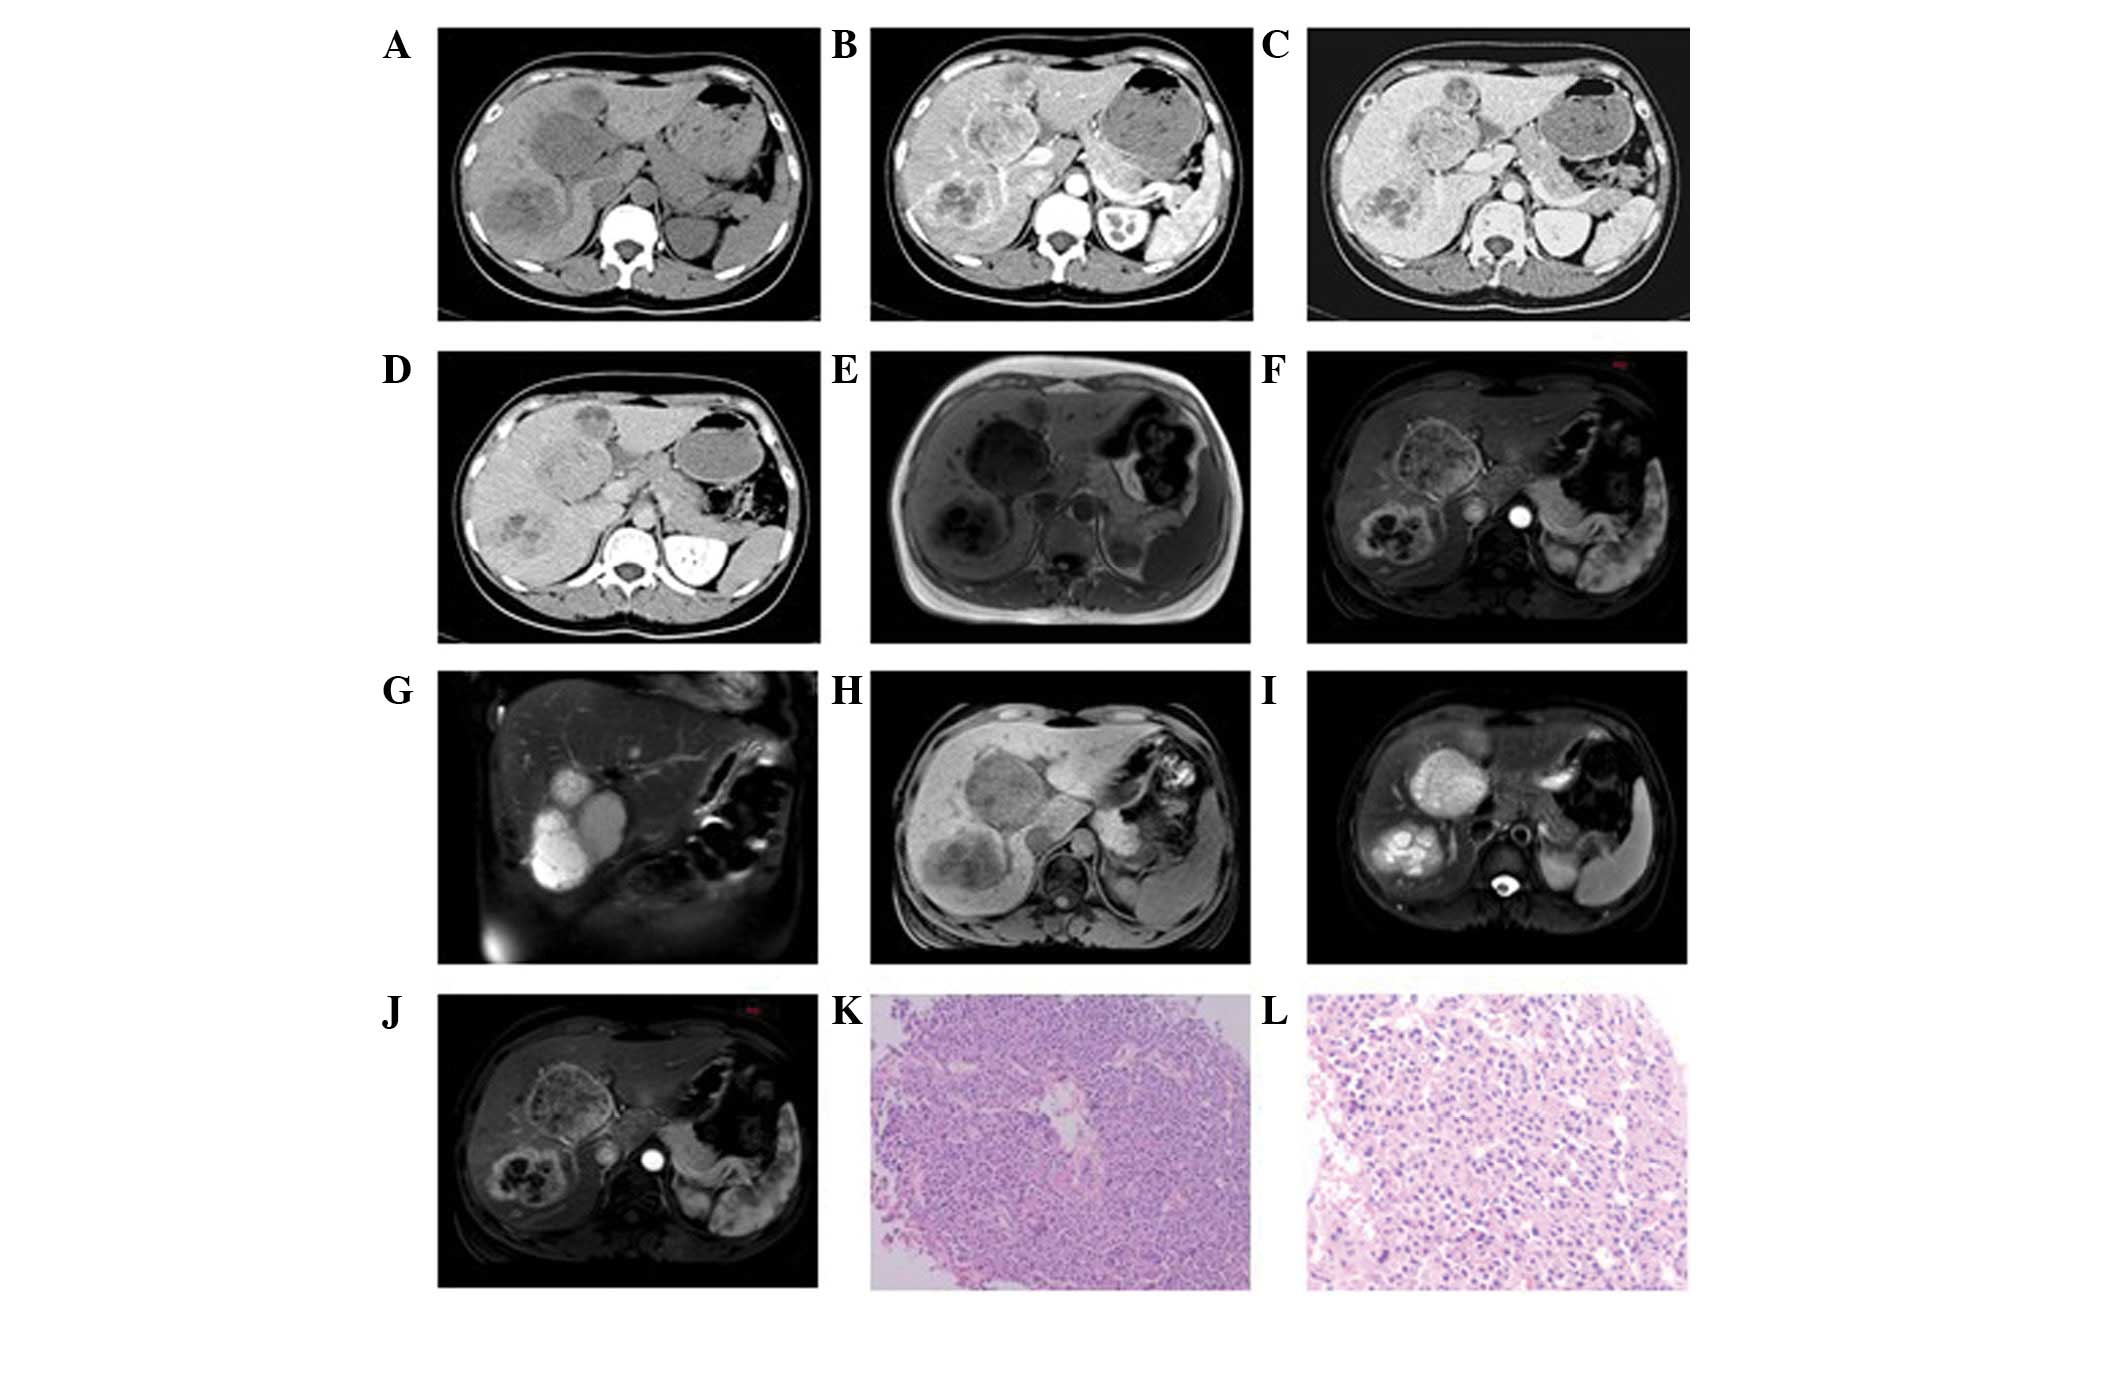

One patient exhibited a single mass in the left hepatic lobe with a maximum cross-section size of 6.5×5.0 cm, clear boundaries and an uneven density (Fig. 1). A liquefied necrotic area in the center of the focus was observed. Enhancement scanning revealed a mild and uneven enhancement at the edge of the mass in the arterial phase, which declined in the portal venous and delayed phases.

Figure 1

Poorly differentiated neuroendocrine carcinoma in a 57-year-old male. (A) Precontrast computed tomography showed a single mass in the left hepatic lobe with a maximum cross-section size of 6.5×5.0 cm, clear boundaries and uneven density. A liquefied necrotic area in the center of the focus was observed. (B) In enhancement scanning, a mild and uneven enhancement was observed at the edge of the mass in the arterial phase. (C and D) A decline in enhancement was observed in the portal venous and delayed phases, respectively. (E and F) Hematoxylin-eosin staining (magnification, ×100 and 200, respectively) showed the poorly differentiated cancer cells to be smaller, with less cytoplasm, angular and trachychromatic nuclei and karyokinesis.

Well-differentiated neuroendocrine carcinoma in a 34-year-old female. (A) Precontrast computed tomography showed multiple lumps of various sizes in the right and left hepatic lobes with a maximum cross-section size of 6×5 cm, clear boundaries and uneven density. A liquefied necrotic area in the center of the largest focus was observed. (B) In enhancement scanning, an annular enhancement was observed in the arterial phase. (C and D) A decline in the enhancement was observed in the portal venous and delayed phases, respectively. (E–J) Magnetic resonance imaging showed multiple long T1 and T2 signal foci in the liver, which were nodular and lumpy which were markedly enhanced. (K and L) Hematoxylin-eosin staining (magnification, ×100 and 200, respectively) revealed morphological diversity of the tumor cells and vessel-like arrangement in parts, with similar morphological features and limited interstitial substance.

Pathology

A number of different types of neuroendocrine tumor were observed in this study, including carcinoid tumors, a well-differentiated neuroendocrine carcinoma and a poorly differentiated neuroendocrine carcinoma. Among these were two cases of carcinoid tumors (Fig. 3E and 3F), three cases of well-differentiated neuroendocrine carcinomas (Figs. 2K and 5E) and four cases of poorly-differentiated neuroendocrine carcinomas (Figs. 1F, 4E and 6J–L). Pathological results showed that the tumor cells were morphologically diverse and that a number of tumor cells formed vessel-like arrangements, with similar morphological features and of little interstitial substance (Figs. 2K, 3E and 3F). Other tumor cells were uniformly small- to medium in size with unclear cytoplasmic boundaries. Additionally, their nuclei were round or regular in shape and arranged irregularly, clustered and flakily or like a chrysanthemum (Fig. 6J–L). The poorly differentiated cancer cells were smaller and with less cytoplasm than the well-differentiated cells. Their nuclei were angular, trachychromatic and karyokinesis was observed (Figs. 1F and 4E). In addition, neuroendocrine granules were observed by electron microscopy (H-7500 Electron Microscope, Hitachi, Tokyo, Japan). The immunohistochemical staining in these tumor cells was positive for CgA and Syn and negative for CEA, HPC and AFP (Table I).